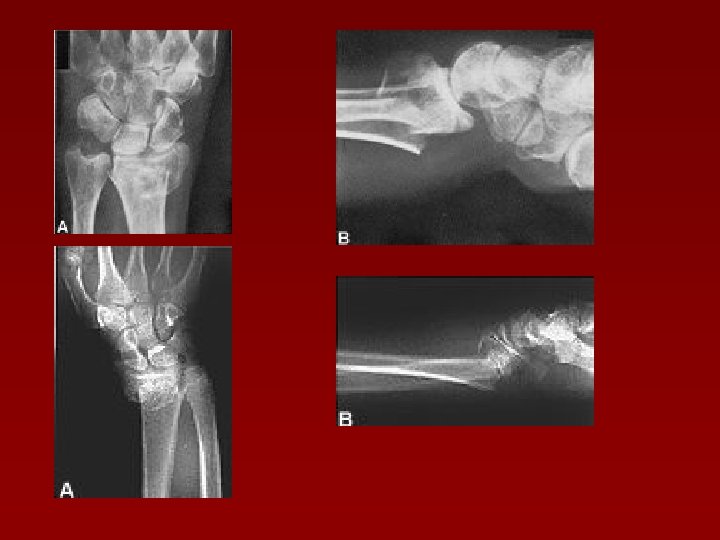

Clasificare Extraarticulare n Tip I – Fără deplasare, stabile n Tip II – Cu deplasare, instabile Intraarticulare n Tip III – Fără deplasare n Tip IV – Cu deplasare - reductibile, stabile - reductibile, instabile - ireductibile

Fracturile intraarticulare Fracturi ale stiloidei radiale – Hutchinson (fig. 1) n Fracturi marginale anterioare – Letenneur (fig. 2) n Fracturi marginale posterioare – Rhea Burton n Fracturi totale – cu traiect de forma literelor “V”, “Y”, “T” n (fig. 1) (fig. 2) Fracturi cu traiect în T

Clasificarea Mayo a fracturilor intraarticulare distale radius Tip I – intraarticulare, fără deplasare (extraarticulare faţă de articulaţia radiocarpiană) Tip II – implică articulaţia radioscafoidiană, cu deplasare Tip III – implică articulaţia radiolunată, cu deplasare Tip IV – implică articulaţia radioscafoidiană şi radiolunată, cu deplasare

Mayo II Mayo IV

Fracturi extraarticulare (supraarticulare) n Fractura Pouteau – Colles n Fractura Goyrand – Smith (Pouteau – Colles inversată)

Unghiurile articulaţiei radio - carpiene

Fractura Pouteau - Colles Fragmentul distal se deplasează : Posterior (---> deformarea în dos de furculiţă) n Proximal (---> angrenarea fragmentelor) n Radial (---> mâna în baionetă) n Tasarea posterioară a fragmentelor